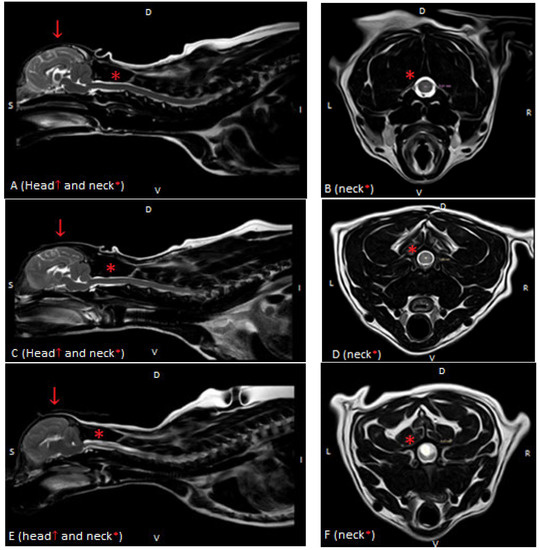

Figure 1.

T2-weighted MR images of the spinal cord in the sagittal (A,C,E) and transverse (B,D,F) planes in three dogs showing: (A,B)—normal spinal cord (Grade 0), (C,D)—central canal dilatation (Grade 1) and (E,F)—syringomyelia (Grade 2). There is severe flattening of the caudal fossa with marked compression of the cerebellum and crowding of the cerebellum (A,C,E).